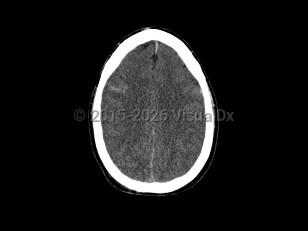

Vomiting, Headache, 50-59 year old Female

Subarachnoid hemorrhageSubarachnoid hemorrhage

Cerebral edemaCerebral edema

Hydrocephalus

Epidural intracranial hematomaEpidural intracranial hematoma

PapilledemaPapilledema

Subdural hematoma

Brain abscessBrain abscess

Posterior fossa hematoma

MeningiomaMeningioma

Subdural empyemaSubdural empyema

CraniopharyngiomaCraniopharyngioma